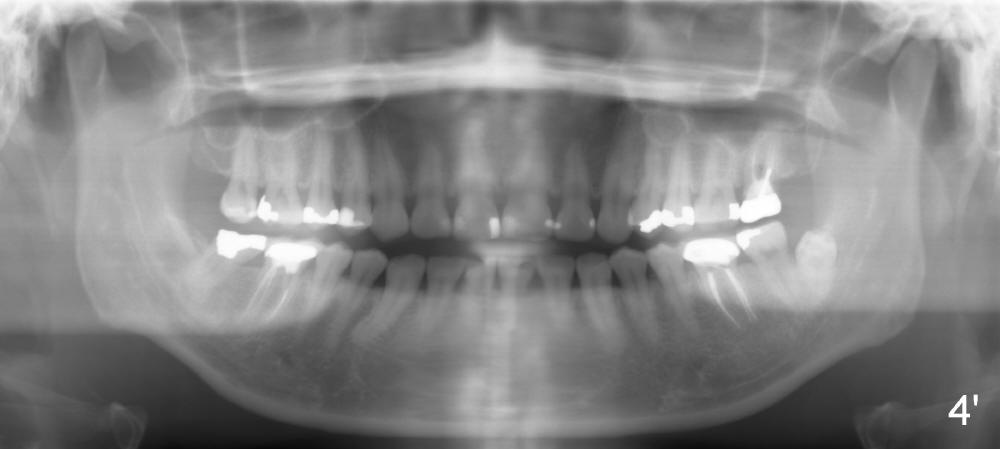

A 42-year-old lady has had problems with the tooth #15 for 4 years. First the crown was dislodged with open margin and furcal lesion (> in Fig.1, P: post; X-ray taken in 2008). Since 2009 (Fig.2,3), the tooth has occasional swelling. The furcal radiolucency remained in the panoramic X-ray (Fig.4 and 4'). Now the patient agrees to have extraction and implant placement.